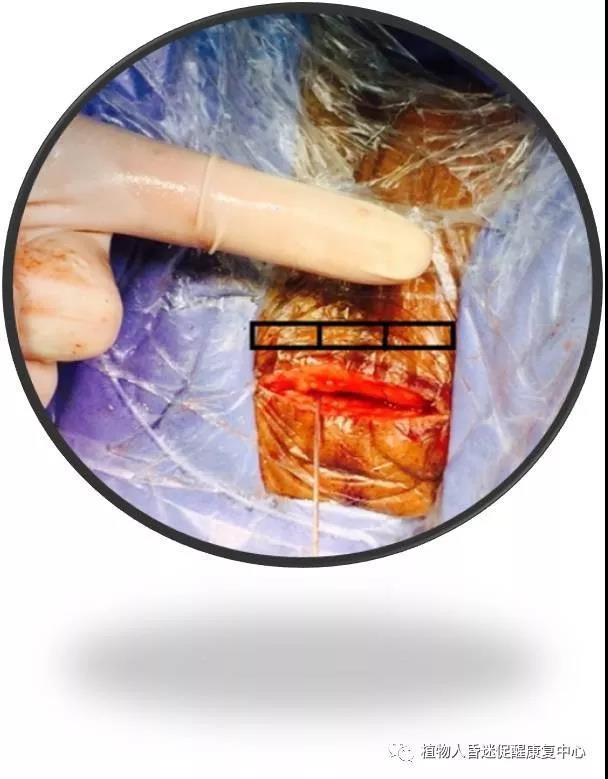

第二、脊髓电刺激(SCS): 作为神经调控治疗方式的一种,近来,对于脊髓电刺激(spinal cord stimulation, SCS)治疗意识障碍的关注逐渐升温。脊髓电刺激(SCS)通过手术放置刺激电极在颈髓C2-C4水平硬膜外正中部,电刺激通过上行性网状结构激活系统及丘脑下部激活系统传达到大脑皮层。有报告认为SCS可以调节局部脑血流量,从而引发作为意识相关神经环路的功能变化。目前较为明确的看法是,SCS可调节增加脑血流量,对于缺血性脑病有益。截至目前,发表的文献和数据共通过SCS治疗了308例PVS患者,51.6%有临床改进。

图6:手术很微创

图7:手术后复查显示电极位于颈椎2-4椎管内。